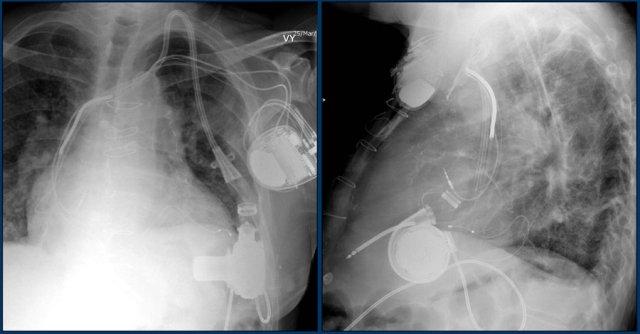

Đây là ví dụ về một ICD với các điện cực đặt tại tiểu nhĩ phải, mỏm thất phải và một điện cực đến thất trái qua tĩnh mạch vành sau.

Có thể nhận biết hai cuộn sốc điện của ICD dưới dạng các dải trắng dày hơn dọc theo đường đi của điện cực.

Các phát hiện bao gồm:

- Hai điện cực thượng tâm mạc kết nối với máy tạo nhịp

- ICD

- Hai điện cực đến mỏm thất phải

- Một điện cực chứa hai cuộn sốc điện

- Van ba lá (mũi tên)

- Van hai lá

Hình ảnh được chụp ngay sau khi đặt ICD.

Có hình ảnh tràn khí màng phổi nhỏ (mũi tên).

Đây là biến chứng thường gặp nhất.